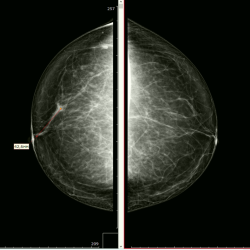

Уважаемые коллеги, как бы вы описали данную картину: очаговая асимметрия или нарушение архитектоники? Регионарно расположенные плеоморфные кальцинаты, правильно? (постаюсь в понедельник ...